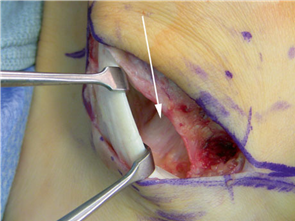

For severe deformities or hypermobility, the Lapidus procedure provides robust stabilization of the medial column. A dorsal or medial incision is utilized over the first TMT joint. The extensor hallucis longus (EHL) is retracted dorsally, and the tibialis anterior tendon is identified and protected at its insertion on the medial cuneiform and first metatarsal base. The TMT joint capsule is incised, and the joint is thoroughly debrided of all articular cartilage using a combination of osteotomes, curettes, and a high-speed burr.

To achieve multiplanar correction, the surgeon must address the sagittal, coronal, and transverse planes. The first metatarsal is plantarflexed to restore the longitudinal arch, rotated out of pronation to realign the sesamoids, and translated laterally to close the IMA. Subchondral drilling or feathering is performed to optimize the biological environment for fusion. Fixation is traditionally achieved with two or three crossed solid or cannulated screws (typically 3.5mm or 4.0mm). Recently, plantar or medial locking plates have gained immense popularity due to their superior biomechanical construct, allowing for earlier weight-bearing. Bone graft or orthobiologics may be packed into the arthrodesis site to stimulate osteogenesis.